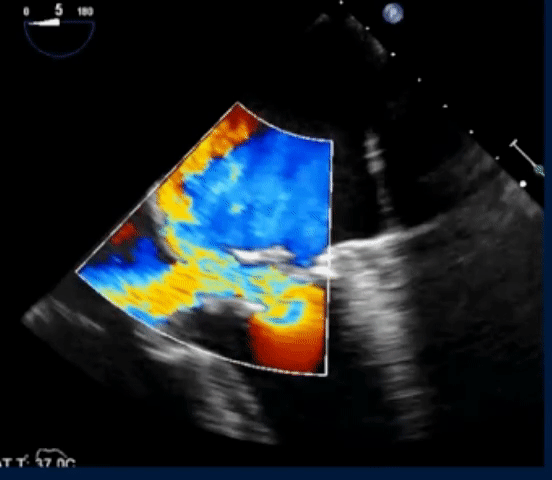

- The following TEE with color Doppler shows a jet of MR going into the LA and RA

- On Color Doppler, we see the blue flow going from LA to the RA through the superior sinus venosus defect: